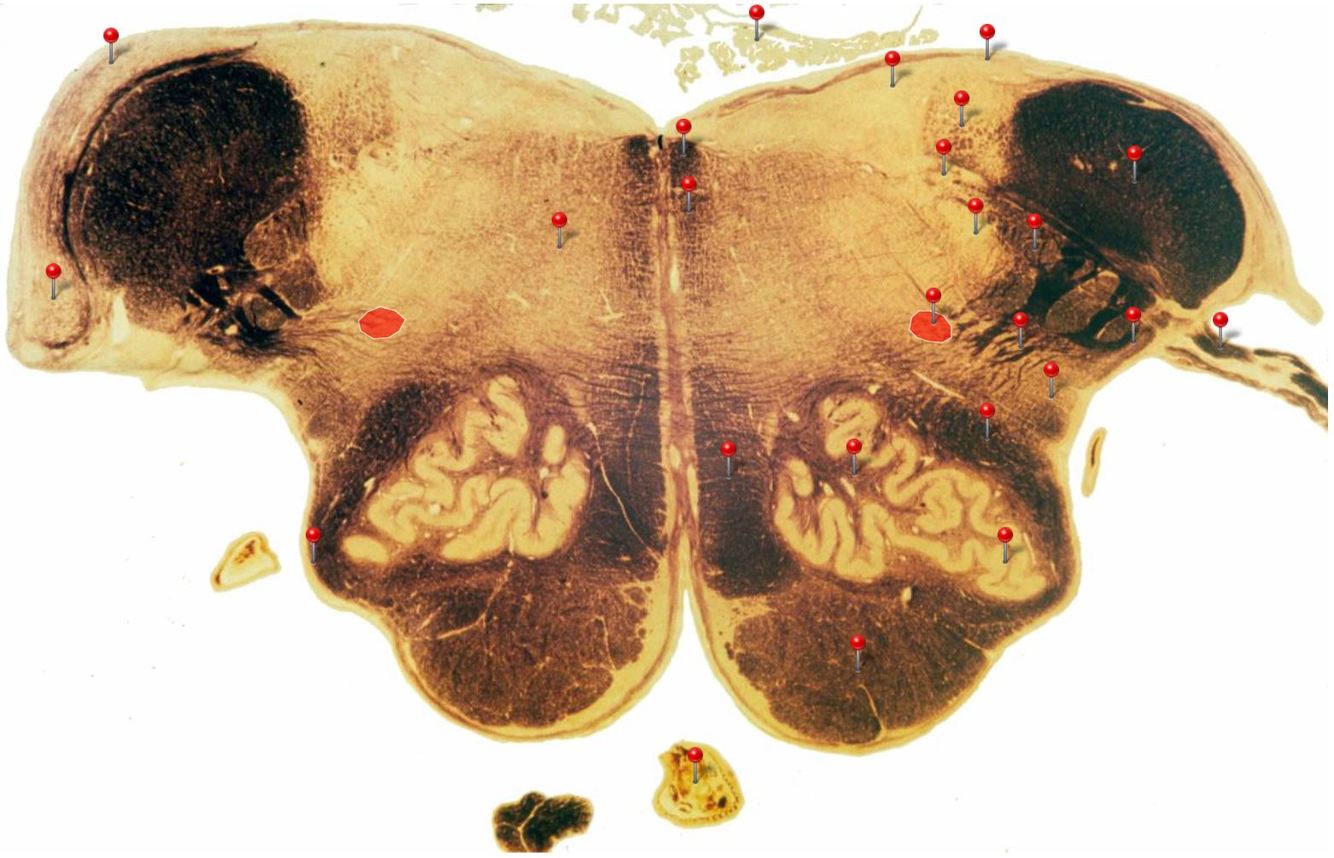

Caudal Midbrain

Transmits auditory info from the inferior colliculus to the medial geniculate nucleus of the thalamus

Edinger Westphal Nucleus

Oculomotor Nerve (CN III)

Supplies extraocular muscles (4 out of the 6; levator palpebrae of upper eyelid, ciliary and sphincter pupillae of the eye)

Corticospinal Tract

Controls precision and speed of skilled movements involving the distal muscles of the contralateral limbs, particularly those of the hands and fingers

5

Q

A

Rubrospinal Tract

Assists in the control of movements of the hands and fingers

6

Oculomotor Nucleus

Neurons give rise to GSE fibres of the oculomotor nerve (CN III) which supply extraocular muscles (4 out of the 6, as well as some fibres of the levator palpebrae superioris m.)

7

Spinothalamic Tract

Transmits pain and temperature sensations from the spinal cord to the thalamus

8

Superior Colliculus

Important relay centre for visual reflexes

9

Periaqueductal Gray (PAG)

Important centre in modulating pain transmission in the spinal cord, particularly in conditions of extreme stress (indirectly through connections with reticular formation)

10

Medial Longitudinal Fasciculus

Pathway through which eye movements are coordinated with changes in head position